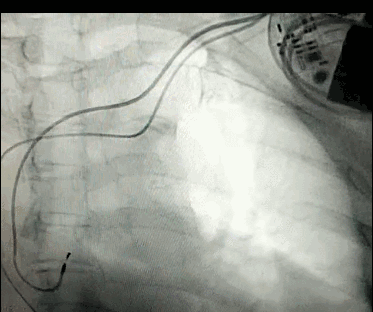

DSA是將造影劑注入需要檢查的血管中,使血管顯露原形,然后通過系統(tǒng)處理,使血管顯示更加清晰,便于醫(yī)生診斷或進行手術(shù)。